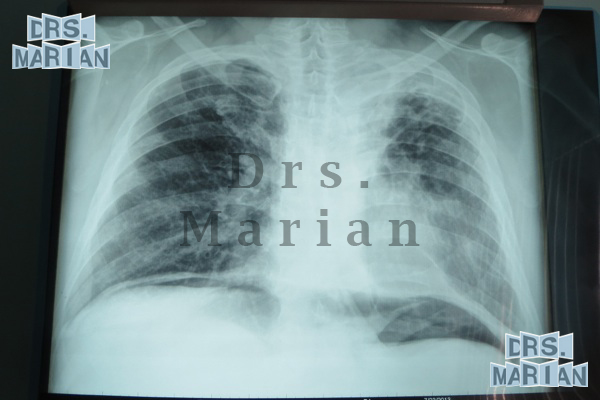

Giant Hernia

This type of hernia deserves a special mention, since the treatment starts from the preoperative management with the intra-abdominal catheter placement for the creation of a pneumoperitoneum (Introduction of air into the abdominal cavity). Depending on the case, if it were to apply one to two weeks before (there are reports of up to 3 months before) This has several functions, such as the pneumatic dissection of adhesions, the increase in volume of the abdominal cavity to facilitate the reintroduction of the viscera during surgery, in addition to providing the proper voltage for closure of the defect hernial sac.

If the pneumoperitoneum is superior to 3 weeks improves the quality of the response to the scarring, which is very important in this type of surgery